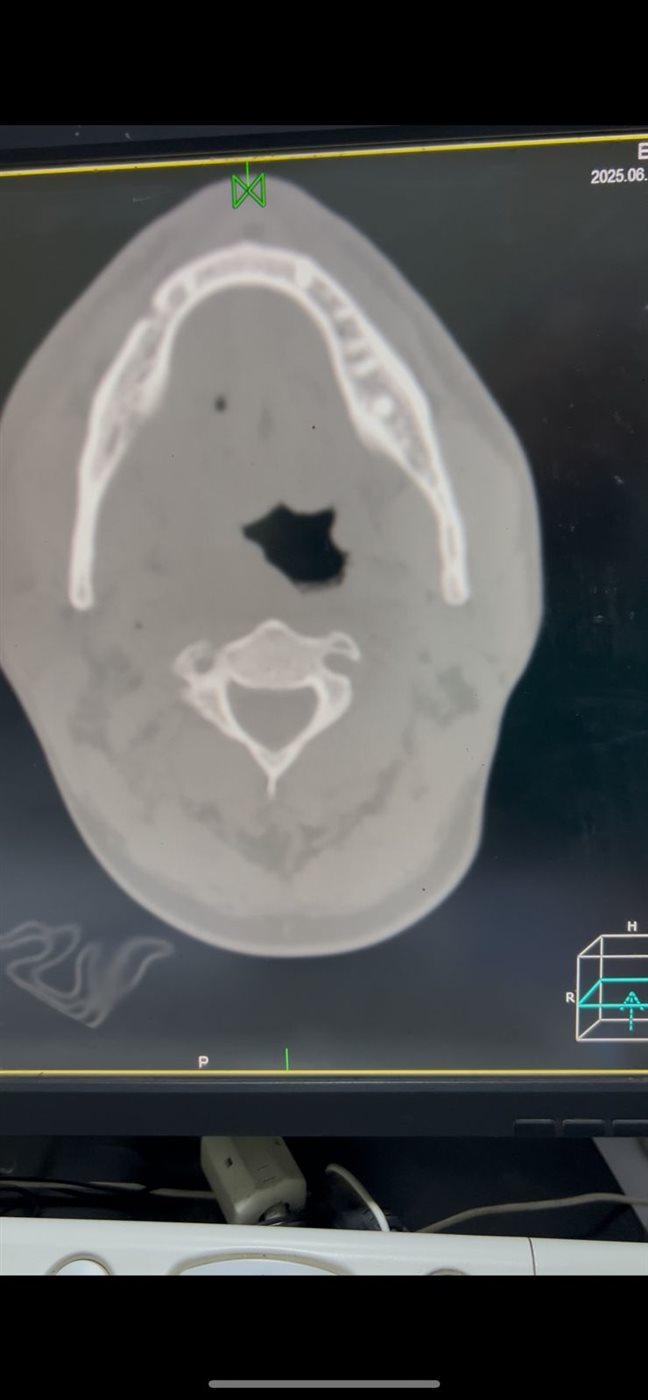

فحص شامل وأشعة للوصول بسبب المشكلة

وكشفت الفحوصات والأشعة عن وجود خراج واسع الانتشار في أرضية الفم والرقبة؛ ما أدى إلى انحراف في مجرى الهواء الطبيعي، وصعوبة بالغة في تركيب أنبوب التخدير.